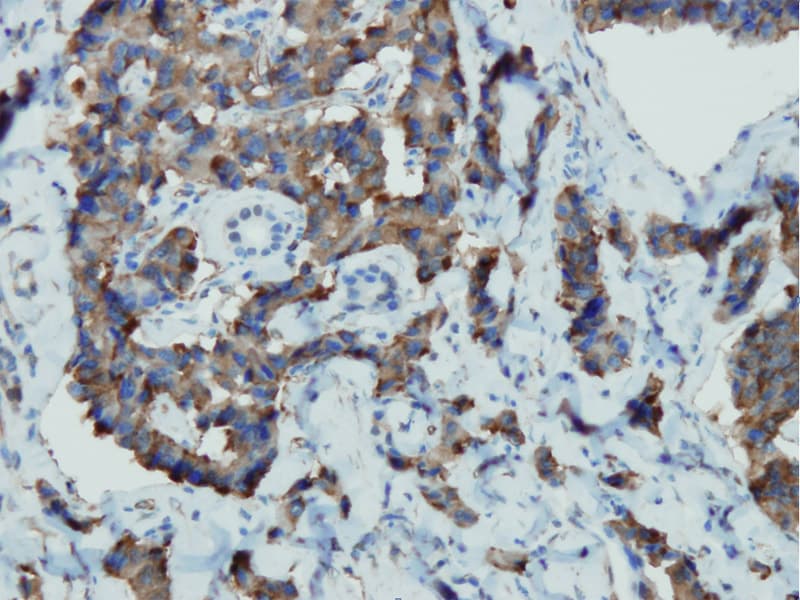

A cromogranina A (CgA) é uma proteína de 86 kDa que é o principal membro da família de granina das glicoproteínas secretoras ácidas localizadas em grânulos neurosecretos de células neuroendócrinas. A cromogranina A mostrou ampla expressão nos tecidos endócrinos, incluindo a hipófise, medula adrenal, tiróide, ilhotas pancreáticas e tracto gastrointestinal. A cromogranina A representa o marcador mais específico de diferenciação neuroendócrina em uso geral. É útil para a identificação de tumores neuroendócrinos.

É um excelente marcador para tumores de carcinoides, feocromocitomas, paragangliomas, e outros tumores neuroendócrinos. A coexpressão da cromogranina A e da enolase específica dos neurónios (NSE) é comum em neoplasias neuroendócrinas. Alegadamente, a co-expressão de certas queratinas e da cromogranina indica a linhagem neuroendócrina. A presença de forte coloração anti-cromogranina e a ausência de coloração anti-queratina deve aumentar a possibilidade de paraganglioma. A co-expressão da cromogranina e da NSE é típica das neoplasias neuroendócrinas. A maioria dos adenomas pituitários e prolactinomas exprimem facilmente a cromogranina.

Pancreas